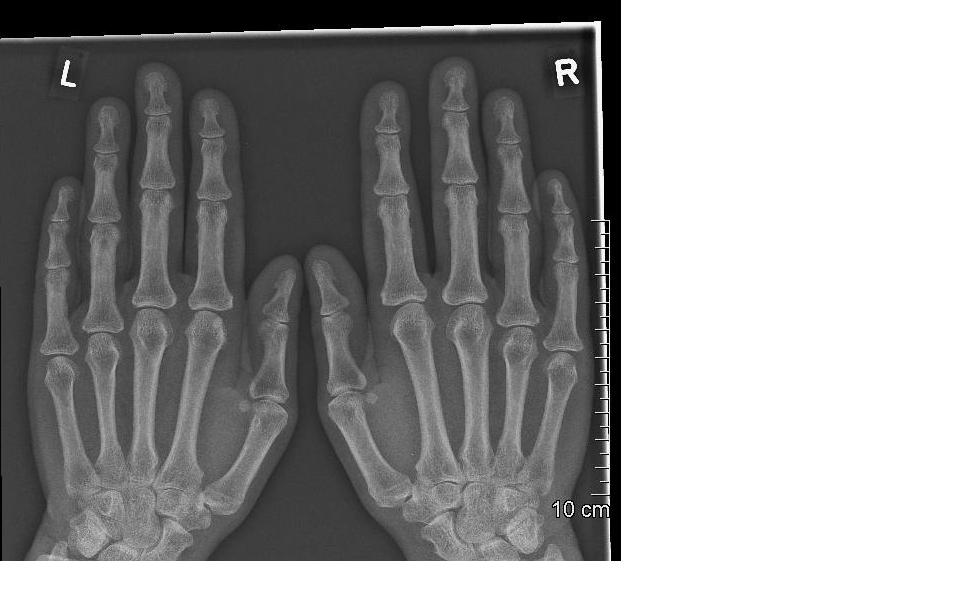

Fingernail X Ray . The hand comprises the metacarpal and phalangeal bones. The series examines in detail the distal, middle and proximal phalanx as well as. Fractures and dislocations are usually straightforward to identify, so long as the potentially injured bone is fully visible in 2 planes. The finger series is comprised, conventionally of a posteroanterior, oblique and a lateral view.

Hand XRay Fingernail X Ray The series examines in detail the distal, middle and proximal phalanx as well as. Fractures and dislocations are usually straightforward to identify, so long as the potentially injured bone is fully visible in 2 planes. The hand comprises the metacarpal and phalangeal bones. The finger series is comprised, conventionally of a posteroanterior, oblique and a lateral view. Fingernail X Ray.

Image Fingernail X Ray The hand comprises the metacarpal and phalangeal bones. Fractures and dislocations are usually straightforward to identify, so long as the potentially injured bone is fully visible in 2 planes. The finger series is comprised, conventionally of a posteroanterior, oblique and a lateral view. The series examines in detail the distal, middle and proximal phalanx as well as. Fingernail X Ray.